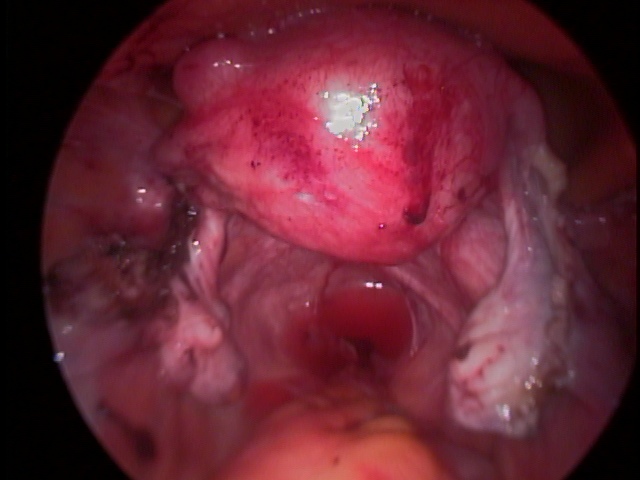

A fecundação do óvulo ocorre na trompa e a partir de então, com os movimentos peristálticos, esse óvulo fecundado é direcionado para o útero, Na gravidez tubária, notamos uma falha nesses movimentos, fazendo com que a gestação se desenvolva no interior da trompa. Com o avançar da gravidez, ocorre a dilatação da trompa, acompanhada de dor importante na parte baixa do abdômen. Eventualmente, essa dilatação ocorre de tal forma que a tuba uterina acaba rompendo (rota) e provocando hemorragia abdominal, exigindo intervenção cirúrgica rápida. A laparoscopia é excelente via de acesso para o tratamento da gravidez tubária.